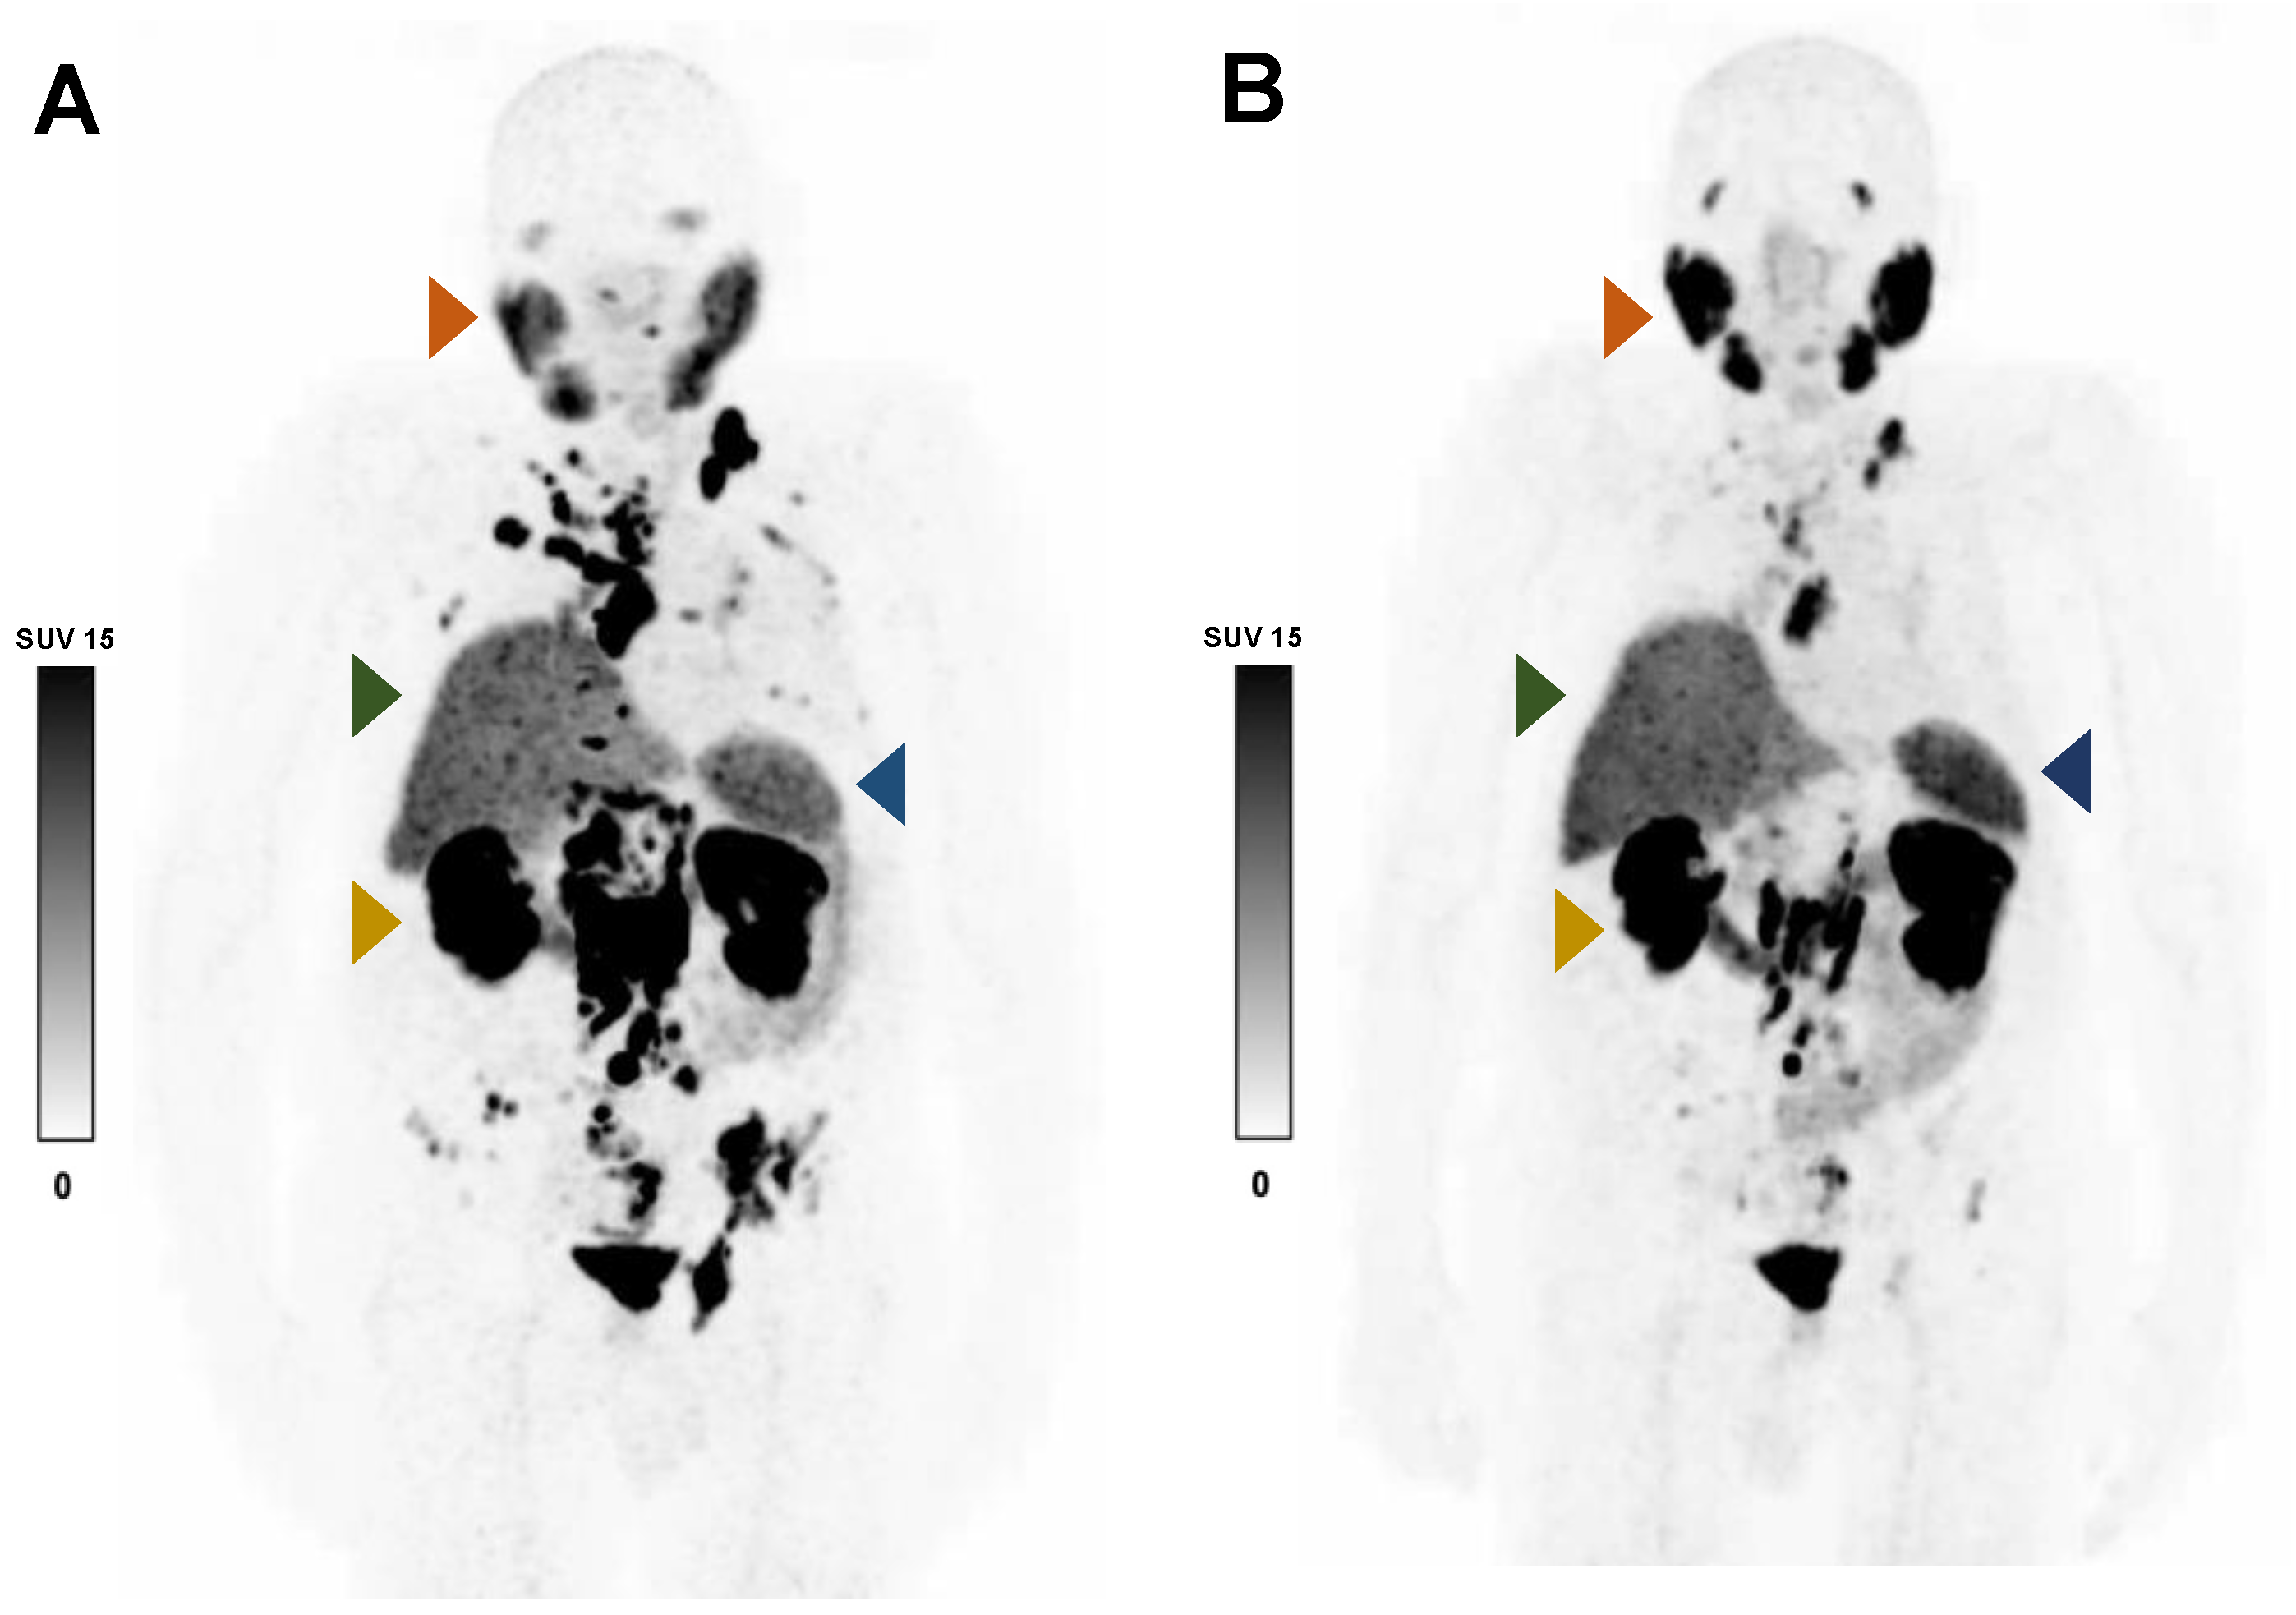

2.4. Calculation of TLP

2.5. 177Lu-PSMA-617 RLT

- Rosar, F.; Wenner, F.; Khreish, F.; Dewes, S.; Wagenpfeil, G.; Hoffmann, M.A.; Schreckenberger, M.; Bartholomä, M.; Ezziddin, S. Early molecular imaging response assessment based on determination of total viable tumor burden in [(68)Ga]Ga-PSMA-11 PET/CT independently predicts overall survival in [(177)Lu]Lu-PSMA-617 radioligand therapy. Eur. J. Nucl. Med. Mol. Imaging 2021, 49, 1584–1594. [Google Scholar] [CrossRef]